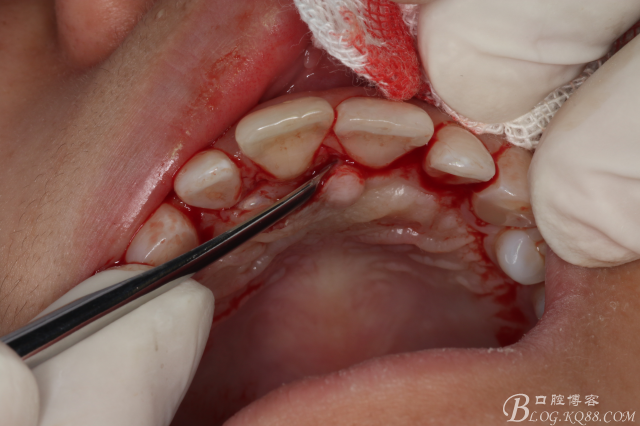

圖9.在切牙管旁邊去骨、暴露出21根尖區(qū)多生牙牙根

圖10.繼續(xù)去骨、發(fā)現(xiàn)多生牙部分位于鼻腭管內(nèi)